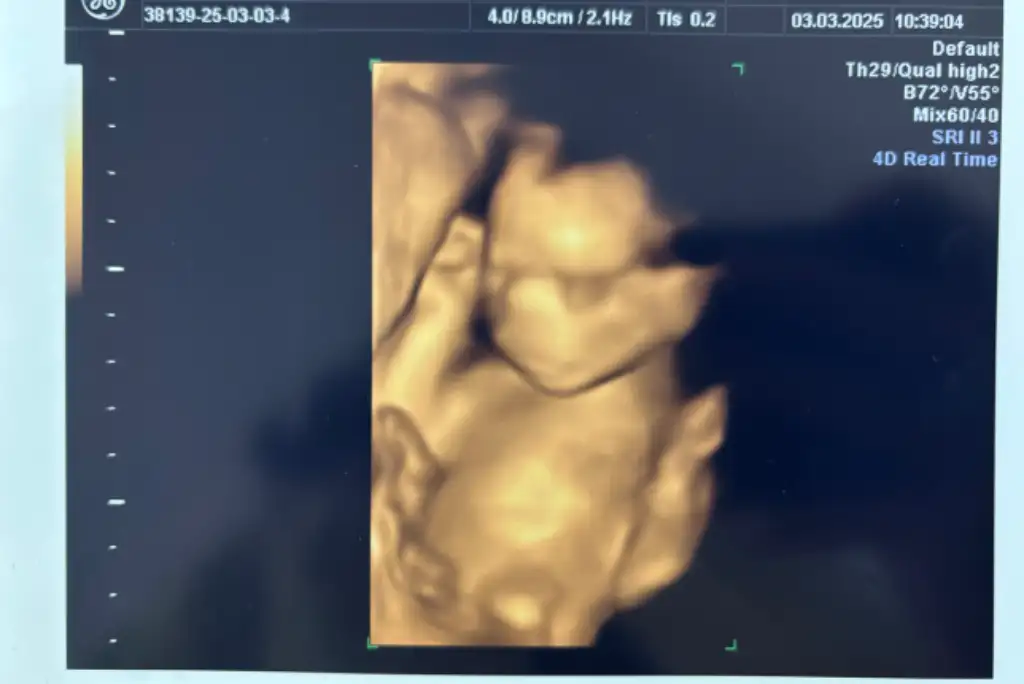

sürekli eli kulağındaydı dr diyor ki telefonla görüşüyor

sürekli eli kulağındaydı dr diyor ki telefonla görüşüyor  ağzını da açıp kapatıyordu gerçekten görüşme yapıyormuş gibi

ağzını da açıp kapatıyordu gerçekten görüşme yapıyormuş gibi